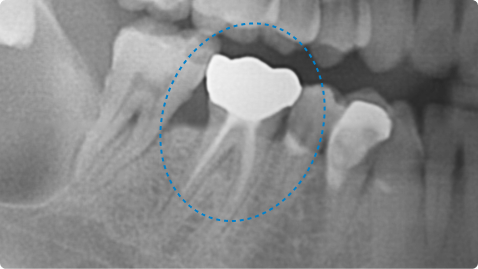

타 치과에서 발치 권유 받은 치아, 잇몸 재생 치료로 자연치아 유지

치료 전

치료 후

치료 내용

• 왼쪽 아래 어금니 잇몸 주머니가 깊어져서 잦은 염증과 불편함 발생

• 엠도게인 활용 잇몸, 뼈 재생 치료 진행

• 치료 후 잇몸뼈가 재생되어 주머니의 깊이가 줄어들고 염증 빈도 감소